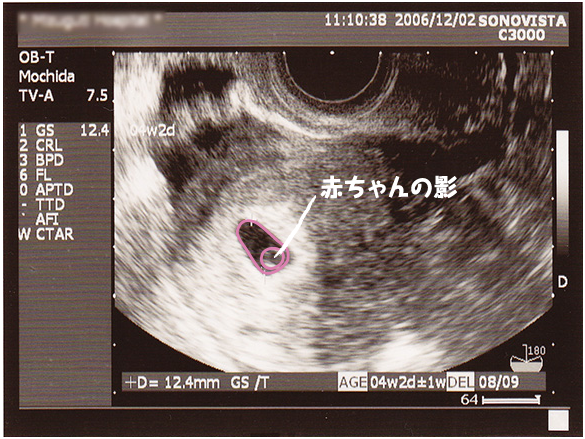

5 産科一般超音波検査 初期編 正常所見4 7週 日本産婦人科医会